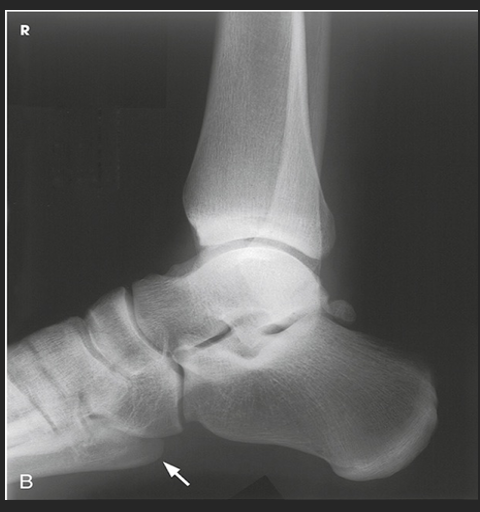

Name this projection.

Lateral calcaneus

What type of projection is it?

Mediolateral

Is the patient on the affected or unaffected side?

Affected

State specifically where the CR enters.

Perpendicular to the calcaneus // 1" distal to the medial malleolus

Which tarsal is in profile?

Calcaneus

Which radiographically significant landmark is open?

Sinus tarsi